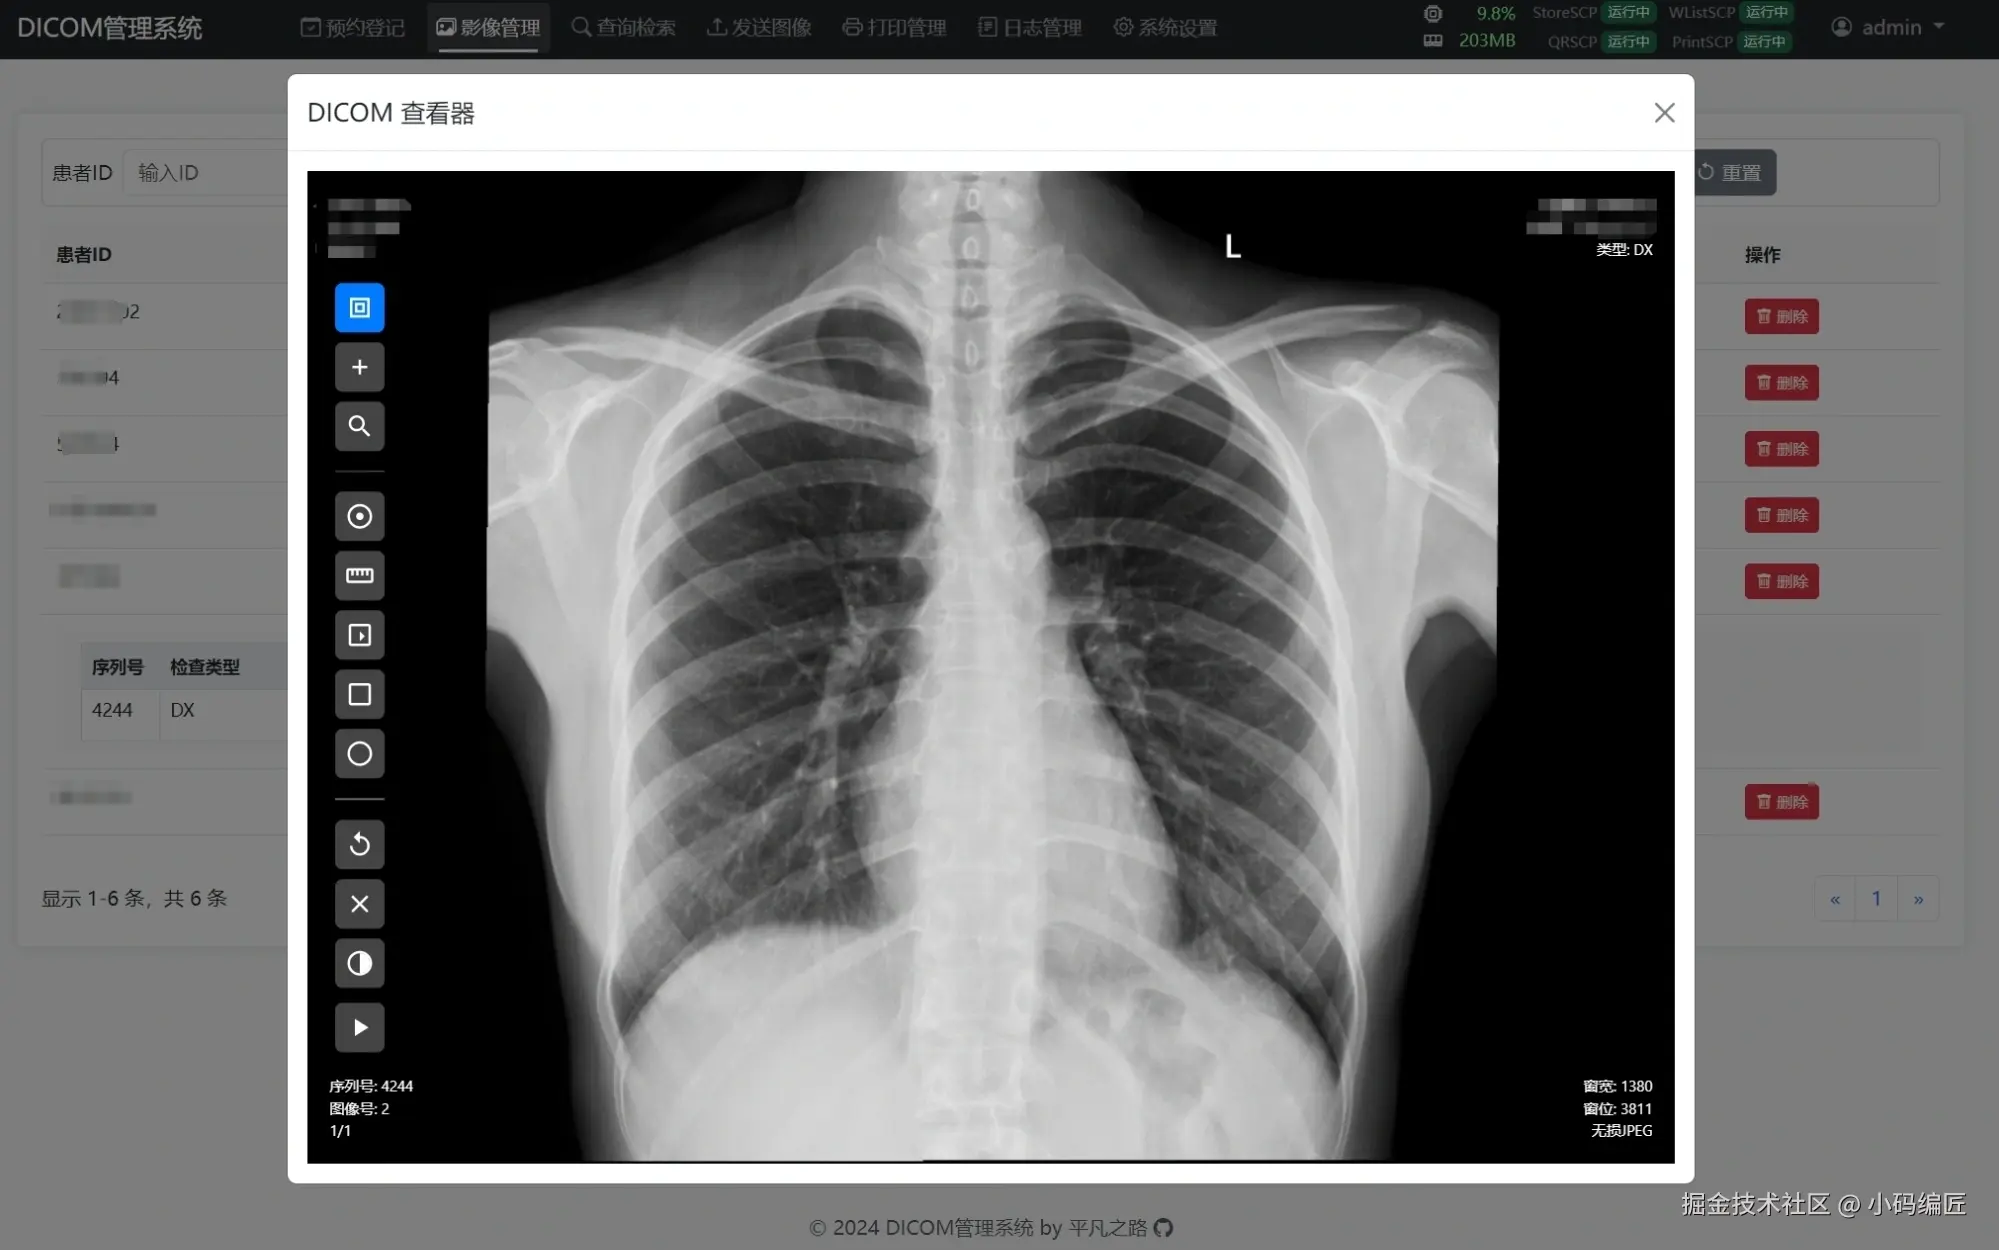

项目效果